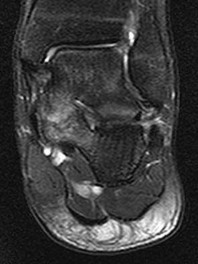

Figures 1a through 1c

Tarsal coalitions occur when primitive mesenchymal cells fail to differentiate and form the

normal articular separations between the tarsal bones of the hindfoot. Overall incidence is difficult to determine because many affected people are minimally symptomatic or asymptomatic. Symptomatic tarsal coalitions typically present in adolescents as a painful flatfoot; however, there are a number of possible presentations, and occasionally symptoms do not appear until adulthood. Most tarsal coalitions are between the calcaneus and the navicular (CN) and the talus and the calcaneus (TC). Although most TC coalitions are across the middle facet, posterior facet coalitions do occur. Plain radiographic evaluation of suspected tarsal coalition is the mainstay for diagnosis. However, coalitions can be bony or fibrous, and making the diagnosis can be difficult. The addition of CT images to distinguish bony definition and MR images to decipher soft tissue can aid in diagnostics. Bony coalitions appear as definite bony bridging between the bones, while fibrous coalitions are suspected when distortion of the bony anatomy is seen. Bony coalitions are best seen on the oblique view (CN) and Harris axial view (TC). There are a number of secondary signs such as the anteater (AE) sign (elongation of the anterior process of the calcaneus as it extends to the navicular as seen on the lateral view [CN]). talar beaking (traction spur of the talar neck thought to result from abnormal stresses as seen on the lateral view [both CN and TN]), and the “C” sign (a continuous cortical contour from the medial talus to the sustentaculum tali [ST]) as seen on the lateral view (TC). A number of newer signs are not as well known, such as a broad mediolateral dimension of the navicular on the anteroposterior (AP) view (the

navicular is wider than the talar head [CN]), nonvisualization of the middle facet on the lateral view (TC), the brick sign (a normal ST is flat, but a distorted ST is enlarged and curved [CN]), and a tapered lateral navicular bone as seen on the AP view (the medial navicular [CN] is much thicker than the lateral navicular).

Figure 1a shows talar beaking (TB), an AE, and an open middle facet (MF). Figure 1b shows a wide navicular (WN), and Figure 1c shows an abnormal articulation between the calcaneus and the navicular, all consistent with a CN coalition.